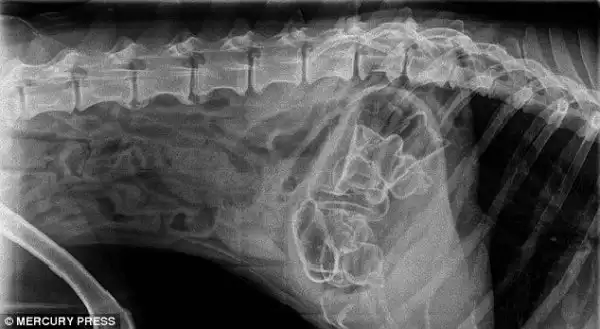

Годовалый кот, который съел 30 резинок для волос

А вот и они, извлеченные из его живота